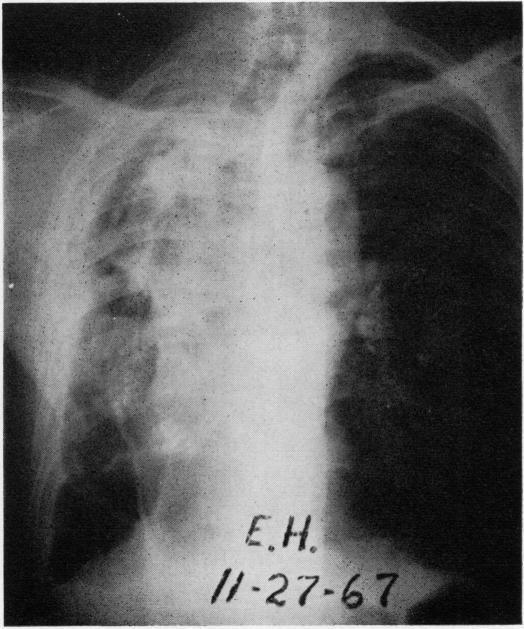

Pulmonary monosporosis is an uncommon form of fungal disease of the lung and bronchorespiratory passages. To date, only six isolated cases have been reported in the literature. It is the purpose of this communication to present the clinical findings, laboratory data, radiographic appearance, and description of the pathology findings in three additional cases identified at the Missouri State Sanatorium. The fungus is present in the soil and has a world-wide distribution. It has been shown to produce localized lesions in the foot called maduromycosis. Pulmonary infection due to this fungus has no characteristic clinical pattern, but the cultural characteristics of permit specific identification. Histologically, the pulmonary involvement shows a variegated non-specific pattern. In the majority of cases, well-defined, predisposing factors are present. A review of the reported six cases and a study of our three cases strengthens our belief that the organism acts as a secondary invader. To date, no mode of therapy has appeared to exert a beneficial influence on the course of the disease. To our knowledge, no clinical trial using any of the antifungal agents has been attempted. Surgical treatment is indicated whenever the lesions are considered resectable. From our observations, we conclude that pulmonary infection with could be recognized more frequently if physicians were more aware of this fungal infection and if the mycology laboratories would take additional care in specific identification.

肺单孢子菌病是肺部和支气管呼吸道真菌病的一种罕见形式。迄今为止,文献中仅报道了6例孤立病例。本报告旨在介绍在密苏里州疗养院发现的另外3例病例的临床发现、实验室数据、影像学表现及病理检查结果。该真菌存在于土壤中,分布于世界各地。它已被证明可在足部产生称为足分支菌病的局部病变。由这种真菌引起的肺部感染没有特征性的临床模式,但该真菌的培养特征可用于特异性鉴定。组织学上,肺部受累表现为多样化的非特异性模式。在大多数病例中,存在明确的易感因素。对已报道的6例病例的回顾以及对我们3例病例的研究强化了我们的观点,即该病原体为继发性入侵者。迄今为止,尚无治疗方式似乎对该病的病程产生有益影响。据我们所知,尚未尝试使用任何抗真菌药物进行临床试验。只要病变被认为可切除,就应进行手术治疗。根据我们的观察,我们得出结论,如果医生对这种真菌感染有更多认识,并且真菌学实验室在特异性鉴定方面更加谨慎,那么肺部感染可能会被更频繁地识别出来。